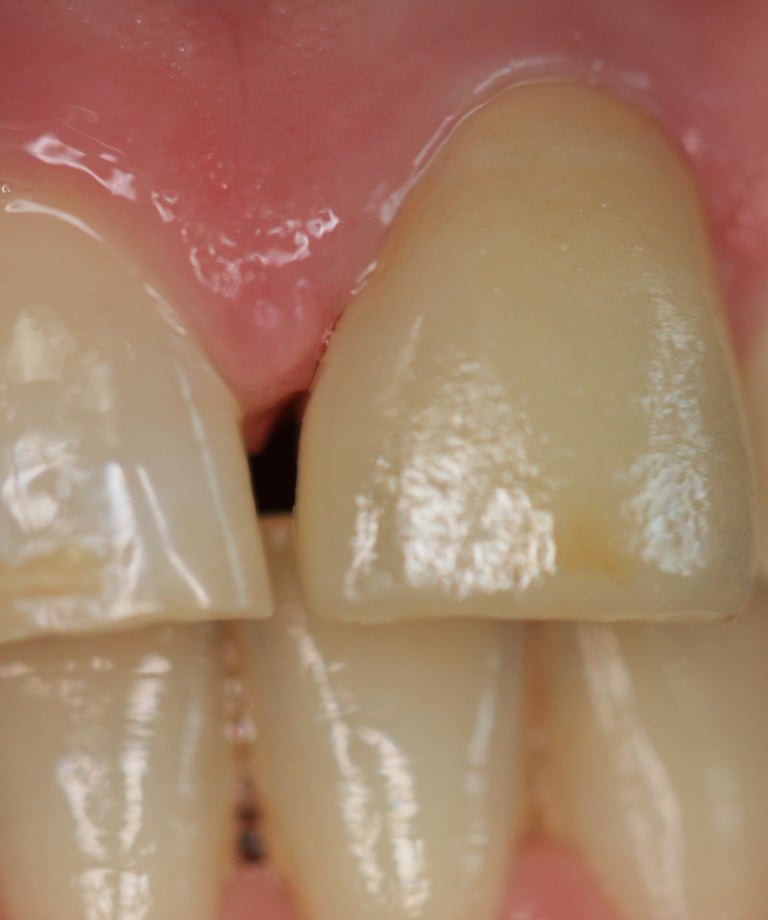

3. Preparazione del Moncone e Impronte

Una volta completato il trattamento endodontico e posizionato il nuovo perno, il moncone è stato preparato con una forma ottimale per la ritenzione della nuova corona. Successivamente, sono state prese impronte digitali per la realizzazione della protesi definitiva.

4. Prova Estetica e Cementazione della Corona Definitiva

La corona definitiva in disilicato di litio è stata progettata per mimetizzarsi perfettamente con i denti naturali in termini di colore, traslucenza e forma. Dopo una prova estetica accurata, la corona è stata cementata utilizzando un cemento adesivo di ultima generazione, garantendo un'adesione duratura e stabile

Corona Estetica

Condizioni Finali

Moncone ritentivo

Trattamento Canalare Congruo